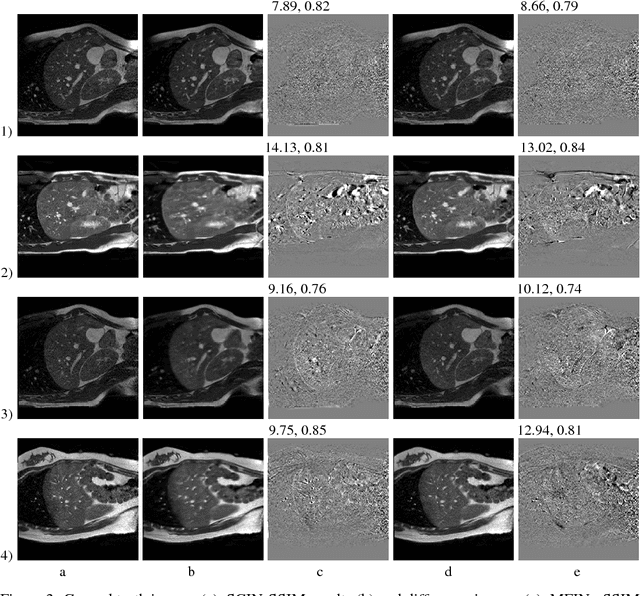

Abstract:Deformable Image Registration (DIR) of MR and CT images is one of the most challenging registration task, due to the inherent structural differences of the modalities and the missing dense ground truth. Recently cycle Generative Adversarial Networks (cycle-GANs) have been used to learn the intensity relationship between these 2 modalities for unpaired brain data. Yet its usefulness for DIR was not assessed. In this study we evaluate the DIR performance for thoracic and abdominal organs after synthesis by cycle-GAN. We show that geometric changes, which differentiate the two populations (e.g. inhale vs. exhale), are readily synthesized as well. This causes substantial problems for any application which relies on spatial correspondences being preserved between the real and the synthesized image (e.g. plan, segmentation, landmark propagation). To alleviate this problem, we investigated reducing the spatial information provided to the discriminator by decreasing the size of its receptive fields. Image synthesis was learned from 17 unpaired subjects per modality. Registration performance was evaluated with respect to manual segmentations of 11 structures for 3 subjects from the VISERAL challenge. State-of-the-art DIR methods based on Normalized Mutual Information (NMI), Modality Independent Neighborhood Descriptor (MIND) and their novel combination achieved a mean segmentation overlap ratio of 76.7, 67.7, 76.9%, respectively. This dropped to 69.1% or less when registering images synthesized by cycle-GAN based on local correlation, due to the poor performance on the thoracic region, where large lung volume changes were synthesized. Performance for the abdominal region was similar to that of CT-MRI NMI registration (77.4 vs. 78.8%) when using 3D synthesizing MRIs (12 slices) and medium sized receptive fields for the discriminator.